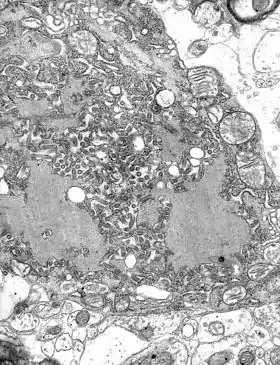

O virião tem em geral a forma de um projétil (arredondada numa extremidade e reta na outra), podendo também ter formato de bacilo (as duas pontas arredondadas), medindo cerca de 170 nm de comprimento por 70 nm de largura.[3]

O revestimento lipídico (4, na imagem) é cercado por uma camada de espículos de glicoproteína, com cerca de 5 a 10 nm de comprimento[1] (2, na imagem). O nucleocapsídeo tem formato helicoidal simétrico (3) e é envolvido por uma camada lipídica (5).[1]